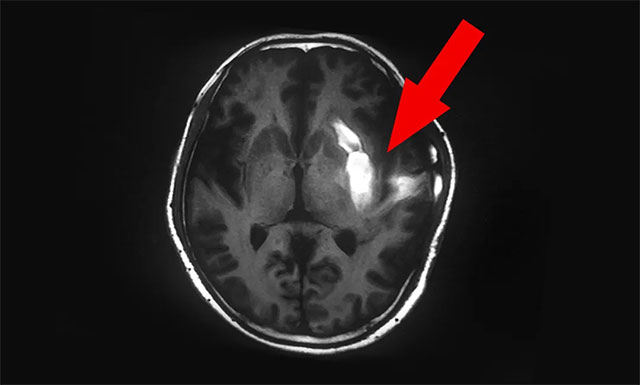

▲ 脑出血部位临近功能区,致使患者右侧肢体偏瘫

季先生因脑出血部位靠近左侧功能区,使其右侧偏瘫;又因出血量大,加上颅内压高;随后,在全麻下行“左侧颅内血肿清除术+脑内减压+去骨瓣减压+脑内压监护术”。手术后第2天,患者又因肺部痰液较多,实施了气管切开术,抗感染治疗,期间患者又出现肝功能不全等并发症。